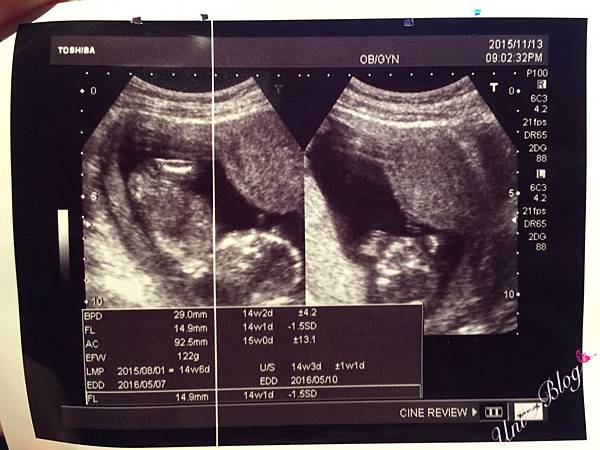

孕媽咪♥22W。高層次超音波-台兒診所

孕媽咪♥20W。羊膜穿刺-中山醫院

孕媽咪♥15W。月子中心挑選~璽悅v.s英倫